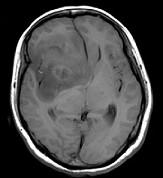

问题 女,32岁,头痛1年,复视4个月,请根据所提供图像,选择最可能的诊断()

选项 A.(右额颞)胶质母细胞瘤 B.(右额颞)多形性黄色星形细胞瘤 C.(右额颞)混合性胶质瘤(星形细胞和少突细胞) D.(右额颞)毛细胞型星形细胞瘤 E.(右额颞)室管膜下巨细胞星形细胞瘤

答案 C